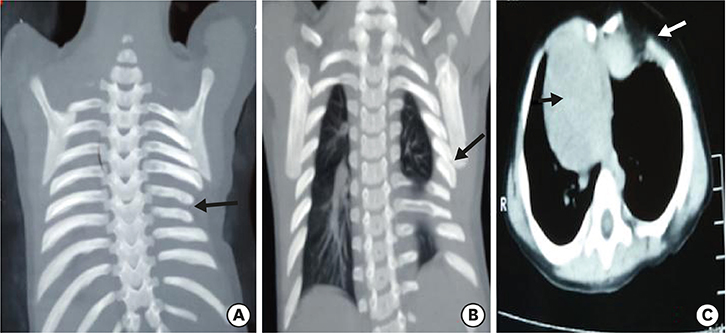

A plain radiograph chest X-ray (Fig. 1) was suspicious of bowel loops or stomach herniating into the left hemithorax. With a working diagnosis of congenital diaphragmatic hernia (CDH)/hiatus hernia, the patient was planned for emergency surgery. The patient was explored through a left subcostal incision. There was no diaphragmatic defect. Although the left diaphragm was higher up in position, it was normal, thick and muscular and not thin and redundant, as in diaphragmatic eventration. There was no paraesophageal or sliding hernia. The spleen was found to be free from its ligamentous attachments. On palpation, of the left chest wall, the lower ribs and costal cartilages were absent along with a portion of the lower sternum. There were deficiency and absence of attachment of pectoral muscles in that region creating a 4×3 cm size muscular defect, which was repaired with non-absorbable sutures. The post-operative period was uneventful and the child was discharged 5 days later. During follow up, the child was evaluated with CT chest with 3D reconstruction (Fig. 2) which was suggestive of dextrocardia, partially fused left 5th and 6th ribs, hypoplastic 7th and 8th ribs, left lung smaller in volume as compared to the right lung, sternal defect and scoliosis of the dorso-lumbar spine. To rule out any associated syndromic conditions, ultrasound (USG) of kidney, ureter, bladder (KUB), 2-dimensional (2D) echocardiography (ECHO) and gastroesophageal reflux (GER) scan were done, which were normal. The child was doing well during the last follow up at 8 months age.

Fig. 2

Computerized tomography with 3-dimensional reconstruction showing hypoplastic 7th and 8th rib (A, black arrow), fused 5th and 6th ribs (B, black arrow), dextrocardia (C, black arrow) and costal cartilage defect (C, white arrow).

Fig. 2 Computerized tomography with 3-dimensional reconstruction showing hypoplastic 7th and 8th rib (A, black arrow), fused 5th and 6th ribs (B, black arrow), dextrocardia (C, black arrow) and costal cartilage defect (C, white arrow).